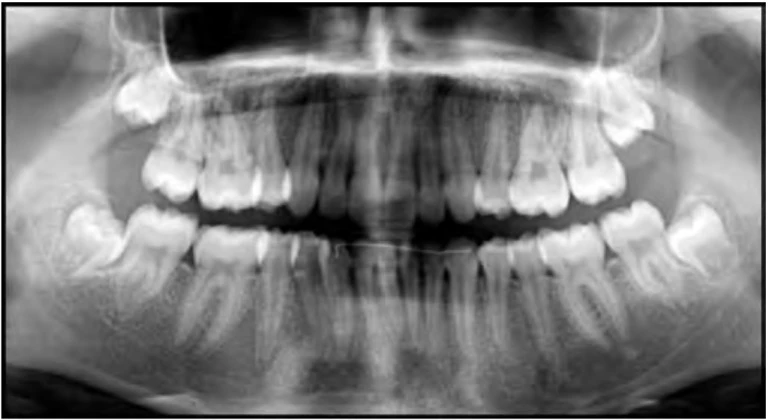

Hình 9E. Răng cối nhỏ thứ nhất hàm trên được nhổ như một phần của kế hoạch điều trị chỉnh nha để đạt được tương quan hạng II răng cối hoàn toàn